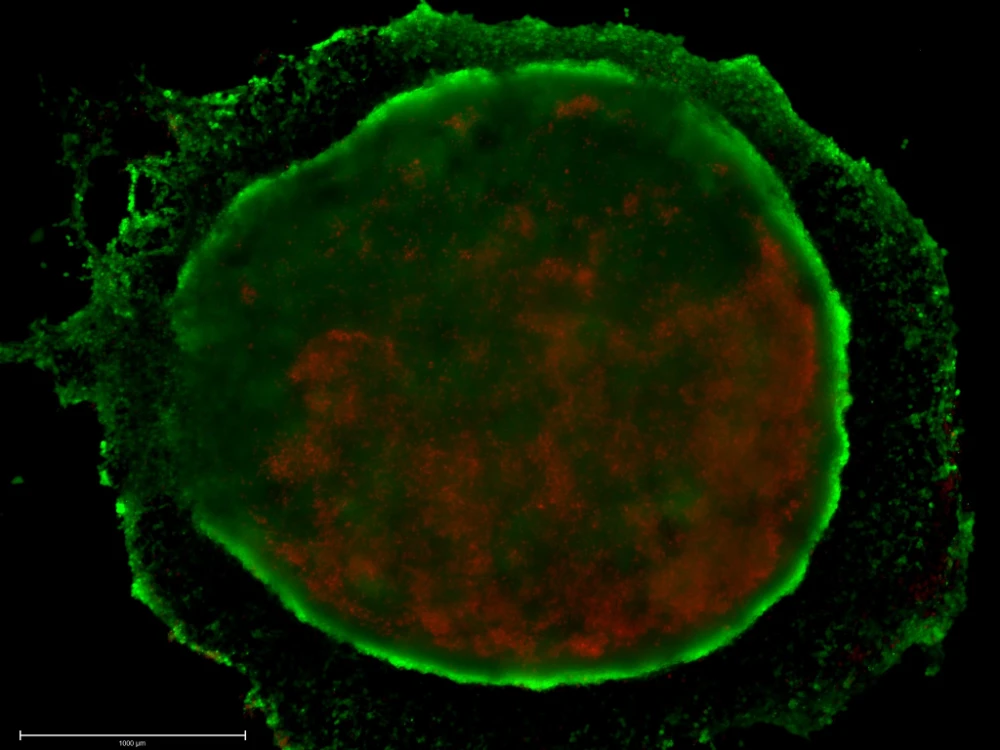

3D cell cultures provide a more accurate representation for studying disease mechanisms by capturing the spatial, biochemical, and mechanical complexity of tissues. 3D cell culture models, including organoids, spheroids, and bioprinted tissues, have been used to understand the roles of cancer-associated fibroblasts in breast cancer, mimic microenvironmental heterogeneity in endometriosis, and model hepatic disease microenvironments.

The gif shows breast cancer cell invasion in TeloCol-10, as described in our Application Note:

Automated Spheroid Invasion Assay Using Collagen from Advanced BioMatrix.